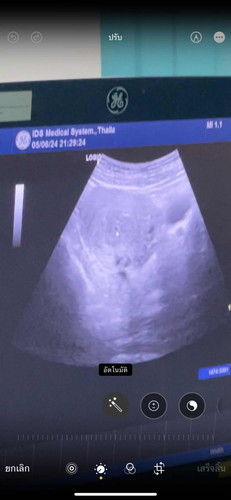

วันที่ 5 มิ.ย. เลยไปตรวจ รพ. หมอว่า ตั้งครรภ์จริง นัดให้มาตรวจใหม่ 18 มิ.ย. ค่ะ แต่เราใจร้อน เลยไปตรวจ ซาวด์ที่คลินิก หมอบอก ยังไม่พบ พบแต่จุดเล็กๆ หมอว่าอาจจะเกิดจาก 1. ครรภ์ยังอ่อนอยู่เลยไม่พบ 2. ตั้งครรภ์นอกมดลูก มีใครเคยเจอแบบนี้มั้ยค่ะ ตอนนี้กังวลมาก 😭#ขอบคุณสำหรับคำคอมเม้นล่วงหน้าค่ะ #ขอความคิดเห็นของคุณแม่หน่อยค่ะ